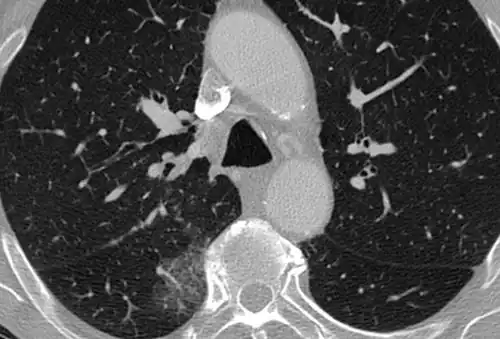

CT image in patient with COVID-19 showing bilateral ground-glass opacities at the periphery of both lungs.

Ground-glass opacity is among the most common imaging findings in patients with confirmed COVID-19.[16][17] One systematic review found that among patients with COVID-19 and abnormal lung findings on CT, greater than 80% had GGOs, with greater than 50% having mixed GGOs and consolidation.[16] GGOs with mixed consolidation has most often been found in elderly populations.[18]

Several studies have described a pattern among initial, intermediate, and hospital discharge imaging findings in the disease course of COVID-19. Most commonly, initial CT imaging reveals bilateral GGOs at the periphery of the lungs. During initial stages, this is most often found in the lower lobes, although involvement of the upper lobes and right middle lobe has also been reported early in the disease course.[16][18] This is in contrast to the two similar coronaviruses, SARS and MERS, which more commonly involve only one lung on initial imaging.[19][20] As the COVID-19 infection progresses, GGOs typically become more diffuse and often progress to consolidation.[11][18] This is sometimes accompanied by the development of a crazy paving pattern and interlobular septal thickening.[18] In many cases the most severe pulmonary CT abnormalities occurred within 2 weeks after symptoms began.[17] At this point, many individuals begin showing resolution of consolidation and GGOs as symptoms improve. However, some patients have worsening symptoms and imaging findings, with further increase in septal thickening, GGOs, and consolidation. These patients may develop lung "white-out" with progression to acute respiratory distress syndrome (ARDS) requiring treatment escalation.[17][21]

Preliminary reports have shown many patients have residual GGOs at time of discharge from the hospital. Due to the novelty of COVID-19, large studies investigating the long-term pulmonary CT changes have yet to be completed. However, long-term pulmonary changes have been seen in patients after recovery from SARS and MERS, suggesting the possibility of similar long-term complications in patients who have recovered from acute COVID-19 infection.[22]